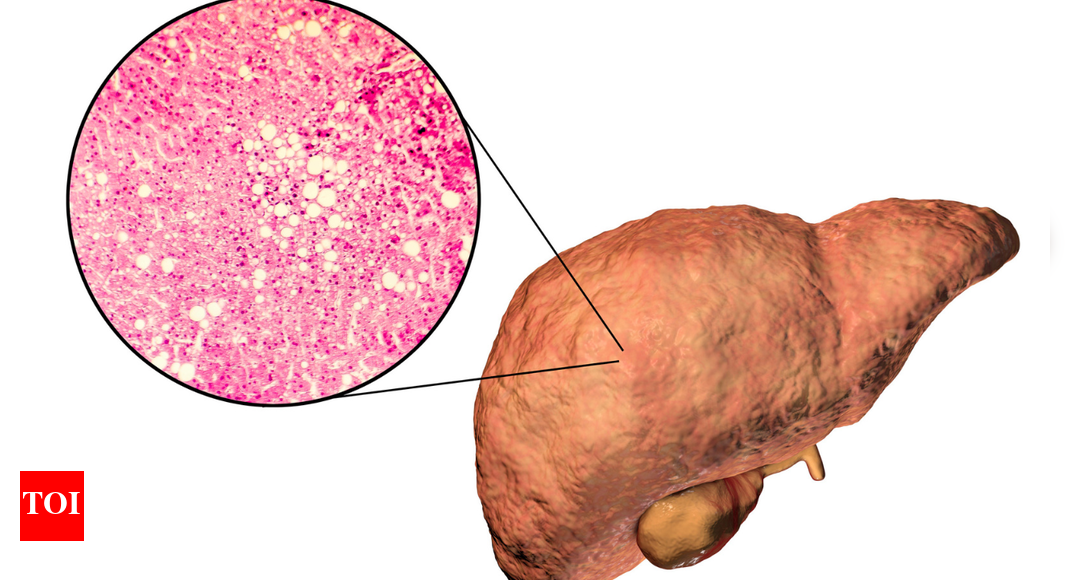

Fatty liver disease is the kind of public health crisis that only a few would be able to escape from. Nearly 38% of adults are now estimated to have Non-Alcoholic Fatty Liver Disease (NAFLD), based on a systematic review published in the Journal of Hepatology.Fatty liver diagnosis, as most of us think, is simply the accumulation of fat in the liver, but to our surprise, it is more than simple fat buildup. Dr. Robert DeBease, a functional medicine expert, says that it’s more complicated than that. In his opinion, a fatty liver issue is more of a matter of what’s going on with the nutrients within your body, and specifically points to copper, vitamin A, and even the sugar in fruit.

First, let’s reconsider the simple concept of fatty liver. Dr. DeBease explains that having this condition isn’t so much about fat. Rather, “hidden triggers,” and these are copper, vitamin A, and fruit sugar (fructose). The liver, is the toxin filtering organ, and its key responsibility is to keep the iron out of the liver and into the blood, thereby keeping the body in motion.This is where it gets confusing. If you don’t have adequate copper or vitamin A, that iron becomes held back in the liver. Visualize the iron as a truckload that can’t depart the warehouse. This inventory begins to destroy liver cells and makes fat start to accumulate. So, in supporting your liver, it’s not merely about consuming less fat—it’s about aiding this iron-shuttling process to function properly.